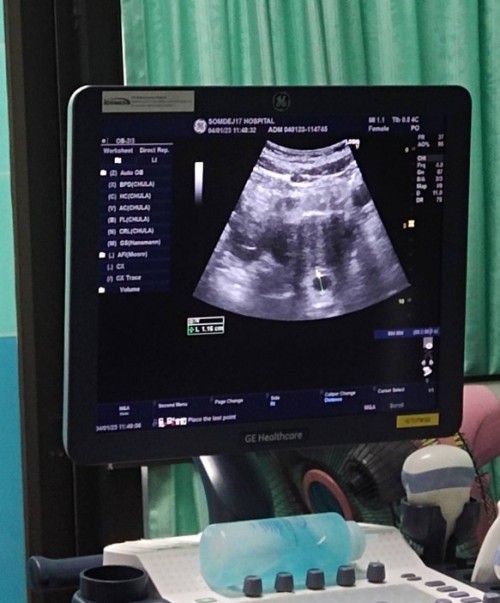

อัลตราซาวด์เห็นเบบี้กี่weeksค่ะ

คุณแม่อัลตราซาวด์เห็นเบบี้น้อยกันตอนกี่weeksกันค่ะ ทางนี้5week 6day ยังมองไม่เห็นเลยค่ะ #ท้องแรกคะ #คุณแม่ๆช่วยแนะนำหน่อยค่ะ

ของเราตอน5-6วีคก็เจอแต่ถุงแบบนี้ค่ะ แต่หมอนัดซาวด์ทุกสัปดาห์จนเจอน้องตัวเล็กๆพร้อมหัวใจเต้นตอน8วีค (ซาวด์หน้าท้องนะคะ) แม่ใจเย็นๆน้าน้องกำลังค่อยๆโตเดี๋ยวก็เจอค่ะ ✌️✌️

เราซาวด์ครั้งแรกตอน5wค่ะแต่ไม่เจอตัวน้องเจอแต่ถุง หมอนัดอีกที10wซาวด์เห็นชัดแจ๋วเลยค่ะ แม่ใจเย็นๆน้าาเดี๋ยวก็ได้เจอน้องค่ะซาวด์ครั้งต่อไป

เราไปตอน 6w ก็ยังไม่เห็นค่ะคุณหมอบอกท้องยังอ่อนมากน้องตัวเล็กเลยมองไม่เห็นง่ายๆ พอไปตอน 8w ก็เห็นค่ะ ใจเย็นๆน๊าคุณแม่อย่าเครียด

ซาว6w+6 เจอแต่ถุงกับไข่แดง หมอนัดอีก2อาทิตย์ไปซาวใหม่ค่ะ แม่อย่าคิดมากนะคะ น้องตัวเท่ามดเองมั้งคะ ส่วนมากเห็น8-12wไปค่ะ

ซาวน์ทางช่องคลอดเจอเด็กและหัวใจตอน6w1dวันค่ะ หมอบอกอายุครรภ์ค่ะ/ แต่ถ้านับวันเองได้6w5dวันค่ะ